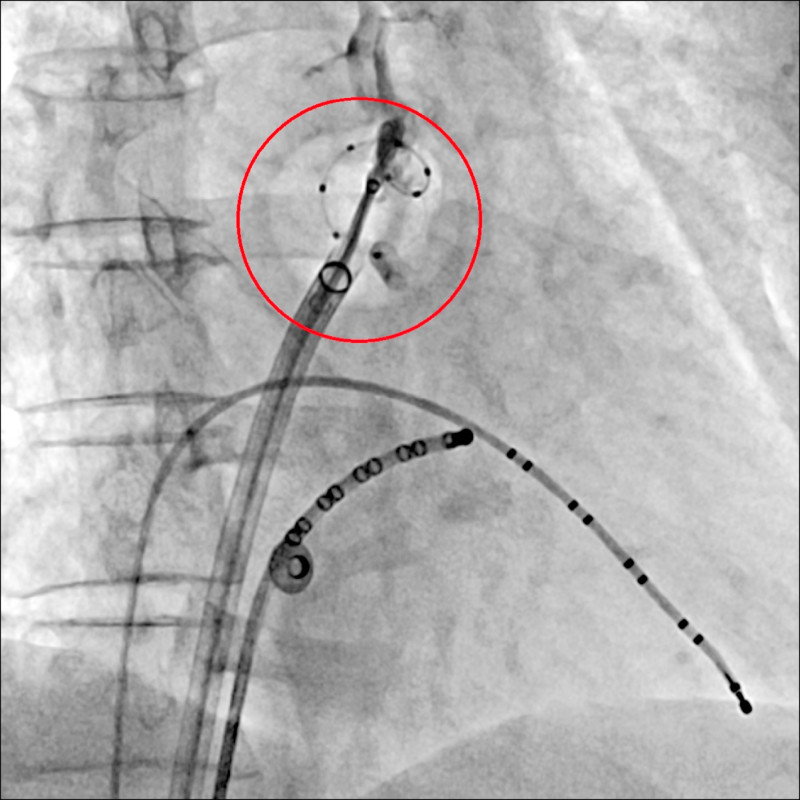

53歲陳先生2年多前感到心臟不適且心悸嚴重,就醫檢查發現他的左心室肌肉較肥厚且心律不整,診斷為心肌病變合併心房顫動,服用藥物舒緩症狀,但去年開始,病患心悸症狀日趨嚴重,就醫後,醫師為陳先生進行冷凍氣球肺靜脈隔離術,手術完成後2天就出院,恢復狀況良好,不再被心悸所困擾。

53歲陳先生兩年多前感到心臟不適且心悸嚴重,就醫檢查發現他的左心室肌肉較肥厚且心律不整,診斷為心肌病變合併心房顫動,服用藥物舒緩症狀,但從去年開始,病患心悸症狀日趨嚴重,生活品質大幅下降,經就醫討論,醫師為陳先生執行冷凍氣球肺靜脈隔離術,手術完成後兩天即出院,恢復狀況良好,不再被心悸所困擾。